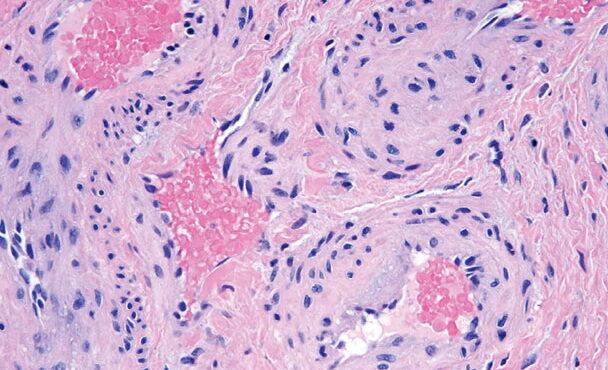

Arsenical keratoses = التقران الزرنيخي ARSENICAL KERATOSES Arsenical keratoses (ArKs) are precancerous lesions found in association with chronic arsenicism. These lesions have the potential to develop into invasive SCC. Arsenic is a ubiquitous element that has no color, taste, or odor. It has the potential to cause characteristic acute and chronic syndromes in persons exposed […]